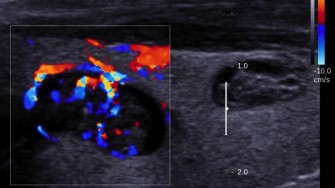

Leur étude a inclus 37 patients (19 hommes), porteurs de nodules > ou = 4 cm (donc plus souvent malins), étiquetés TFT, et sans ganglions perçus cliniquement ni sur l’échographie. Tous ces nodules étaient suspects sur les données, échographiques, et/ou scintigraphiques, cytologiques et biologiques (thyroglobulinémie > ou = 800 ng/ml).